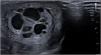

Ecográficamente se observa una tumoración testicular izquierda multiquística (fig. 2), por lo que se completa el estudio con marcadores tumorales: alfa-fetoproteína (AFP) > 20.000 ng/mL, beta HCG negativa < 1,2 mU/mL, testosterona 0,3 ng/mL e inhibina B 72 pg/mL sugiriendo un TCGJ.